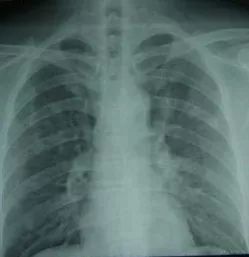

病情分析: 你好,你说的应该的肺部的毛玻璃结节,是胸部X线片报告结果,常见的原因有肺结核、肺癌、肺脓肿等,建议做胸部CT来进一步明确诊断。然后针对性的治疗。

左肺下部见磨砂玻璃状0.5cm小结节 在今年8.30的CT平扫显示左肺下部有一个约0.5cm的磨砂玻璃状小结节,右肺见条索影,并见有几个微小结节。另外在2011-12-7的CT平扫中显示左肺下部有一个约0.5cm的磨砂玻璃状小结节,右肺见条索影,但未提到见有微小结节。 ,以便医生了解病情,给出诊疗建议。